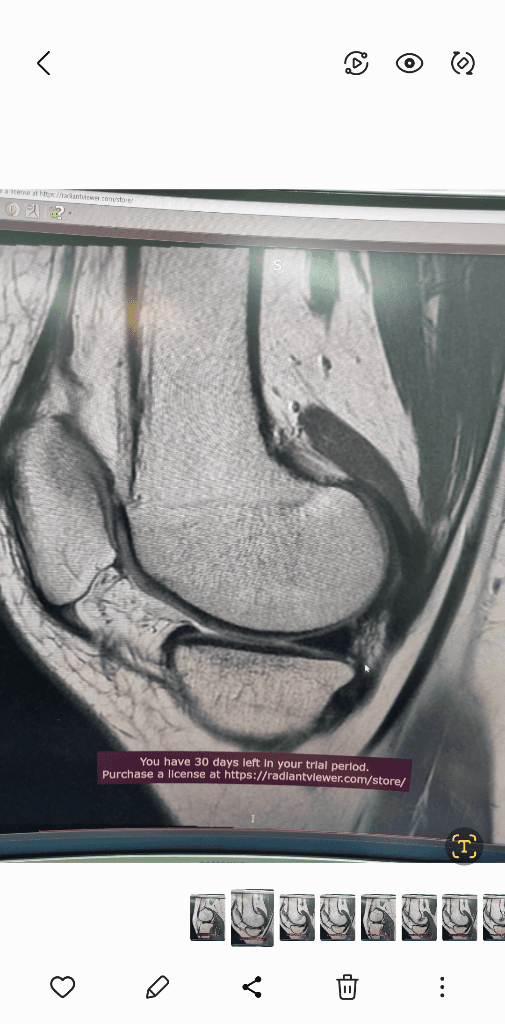

MRI는 신호가 다른 다른 사진들이 있을겁니다.

그런걸 종합적으로 판단해야 정확히 알수 있습니다.

검사한 병원에 판독요청하세요.